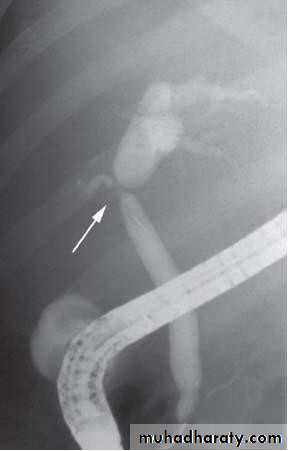

• ENDOSCOPIC RETROGRADE

• CHOLANGIOPANREATOGRAPHY (ERCP)

•  Side veiwing endoscopie

•  Cannulation of ampulla of Vater

•  Injection of contrast to visualize the bile

• ducts

•  Also bile can be taken for cytological and

• microbiological tests

•  Brushings from strictures

• ERCP